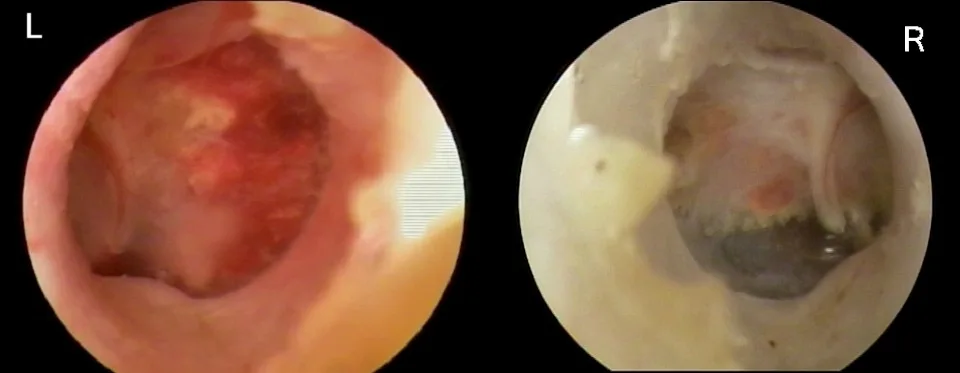

Confirmation of solid or opaque mass filling the bulla (Figure 3)

FIGURE 3 This cat has a solid mass of tissue in the right middle ear. Myringotomy and cytology revealed lymphoma.